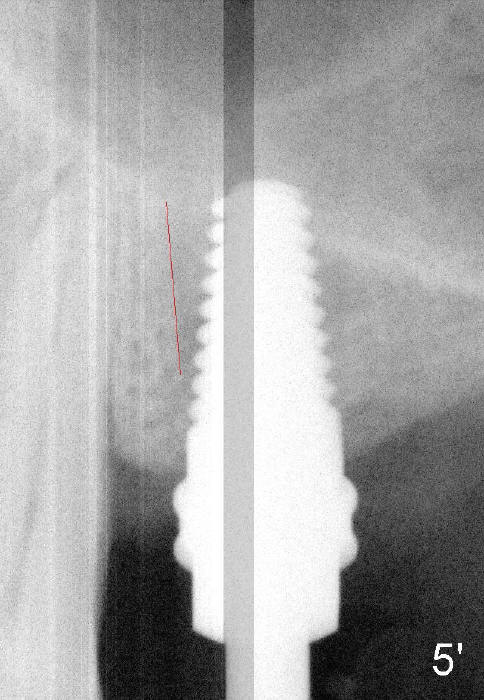

Fig.1: preop; Fig.4: 3.5x11 mm drill; Fig.5': 4.5x11 mm tap; Fig.6: 4.5x11 mm implant. Red line: original mesial apical outline of osteotomy. It shows that it is possible to change trajectory at late stage of osteotomy by changing angulation and position of burs, paying attention of orientation of tap and implant while inserting them.